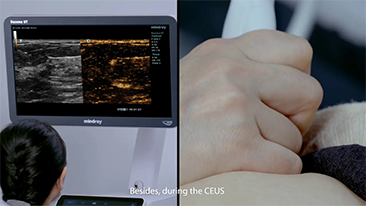

Com que clareza vocĂȘ consegue ver um fĂgado?

Para les?es hepĂĄticas focais, tais como hemangioma ou c?ncer hepĂĄtico, a imagem de contraste por ultrassom desempenha um papel significativo. A tecnologia de imagem por contraste UWN+ n?o linear ultralarga pode ajudar a obter melhor penetra??o e maior rela??o contraste-tecido, com menor MI e maior observa??o do tempo de perfus?o.